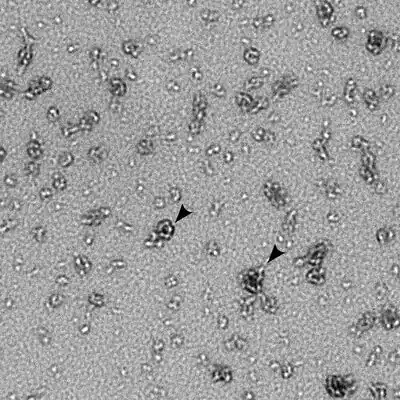

Chlamydia trachomatis is a gram-negative bacterium that can replicate only within a host cell.[3] Over the course of the C. trachomatis life cycle, the bacteria take on two distinct forms. Elementary bodies are 200 to 400 nanometers across, and are surrounded by a rigid cell wall that allows them to survive outside of a host cell.[3][4] This form can initiate a new infection if it comes into contact with a susceptible host cell.[3] Reticulate bodies are 600 to 1500 nanometers across, and are found only within host cells.[4] Neither form is motile.[4]

Like other Chlamydia species, C. trachomatis has a life cycle consisting of two morphologically distinct forms. First, C. trachomatis attaches to a new host cell as a small spore-like form called the elementary body.[5] The elementary body enters the host cell, surrounded by a host vacuole, called an inclusion.[5] Within the inclusion, C. trachomatis transforms into a larger, more metabolically active form called the reticulate body.[5] The reticulate body substantially modifies the inclusion, making it a more hospitable environment for rapid replication of the bacteria, which occurs over the following 30 to 72 hours.[5] The massive number of intracellular bacteria then transition back to resistant elementary bodies, before causing the cell to rupture and being released into the environment.[5] These new elementary bodies are then shed in the semen or released from epithelial cells of the female genital tract, and attach to new host cells.[6]

Elementary bodies are generally present in the semen of infected men and vaginal secretions of infected women.[6] When they come into contact with a new host cell, the elementary bodies bind to the cell via interaction between adhesins on their surface and several host receptor proteins and heparan sulfate proteoglycans.[3] Once attached, the bacteria inject various effector proteins into the host cell using a type three secretion system.[3] These effectors trigger the host cell to take up the elementary bodies and prevent the cell from triggering apoptosis.[3] Within 6 to 8 hours after infection, the elementary bodies transition to reticulate bodies and a number of new effectors are synthesized.[3] These effectors include a number of proteins that modify the inclusion membrane, called Inc proteins, as well as proteins that redirect host vesicles to the inclusion.[3] 8 to 16 hours after infection, another set of effectors are synthesized, driving acquisition of nutrients from the host cell.[3] At this stage, the reticulate bodies begin to divide, coinciding with the expansion of the inclusion.[3] If several elementary bodies have infected a single cell, their inclusions will fuse at this point to create a single large inclusion in the host cell.[3] From 24 to 72 hours after infection, reticulate bodies transition to elementary bodies which are released either by lysis of the host cell or extrusion of the entire inclusion into the host genital tract.[3]